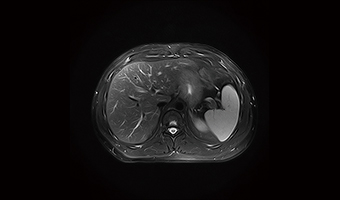

CSPI ivmesini kullanarak, nefes tutmalı abdominal yüksek hızlı, yüksek çözünürlüklü sekansları tamamlamak mümkündür.

Gerçek 24/32 Kanal Sistemi